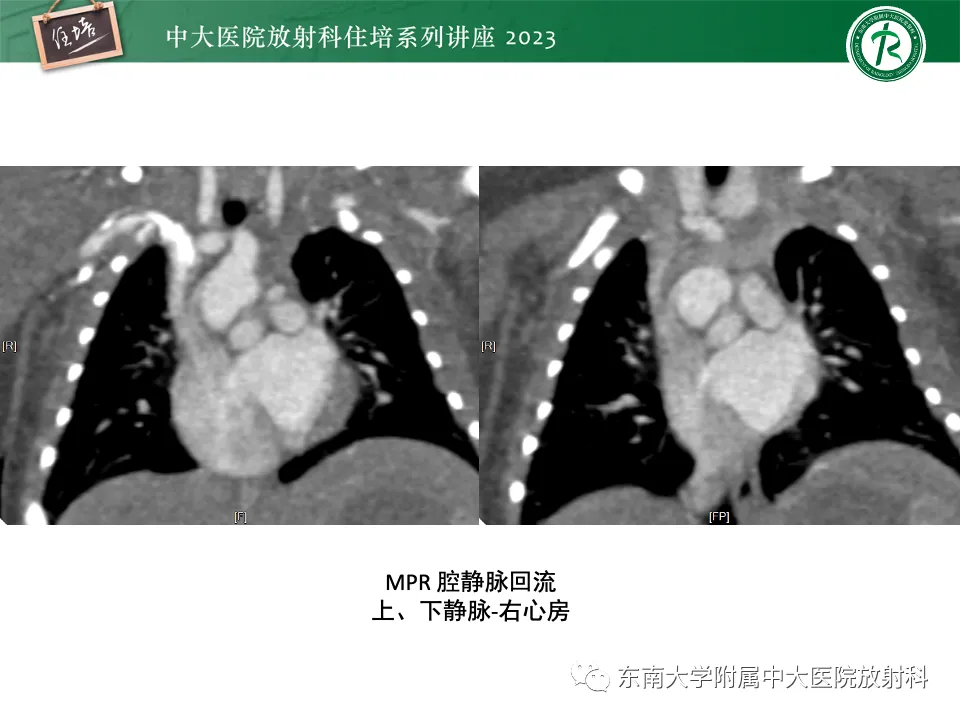

>精美课件丨心脏大血管常见疾病CT图像后处理要点

精美课件丨心脏大血管常见疾病CT图像后处理要点

来源:东南大学附属中大医院医学影像科